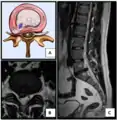

Nucleus herniating through tear in annulus (with MRI)[9]

- Magnetic resonance imaging is the gold standard study for confirming a suspected LDH. With a diagnostic accuracy of 97%, it is the most sensitive study to visualize a herniated disc due to its significant ability in soft tissue visualization. MRI also has higher inter-observer reliability than other imaging modalities. It suggests disc herniation when it shows an increased T2-weighted signal at the posterior 10% of the disc. Degenerative disc diseases have shown a correlation with Modic type 1 changes. When evaluating for postoperative lumbar radiculopathies, the recommendation is that the MRI is performed with contrast unless otherwise contraindicated. MRI is more effective than CT in distinguishing inflammatory, malignant, or inflammatory etiologies of LDH. It is indicated relatively early in the course of evaluation (<8 weeks) when the patient presents with relative indications like significant pain, neurological motor deficits, and cauda equina syndrome. Diffusion tensor imaging is a type of MRI sequence used for detecting microstructural changes in the nerve root. It may be beneficial in understanding the changes that occur after herniated lumbar disc compresses a nerve root, and might help in differentiating the patients that need surgical intervention. In patients with a high suspicion of radiculopathy due to lumbar disc herniation, yet the MRI is equivocal or negative, nerve conduction studies are indicated.[44] T2-weighted images allow for clear visualization of protruded disc material in the spinal canal.